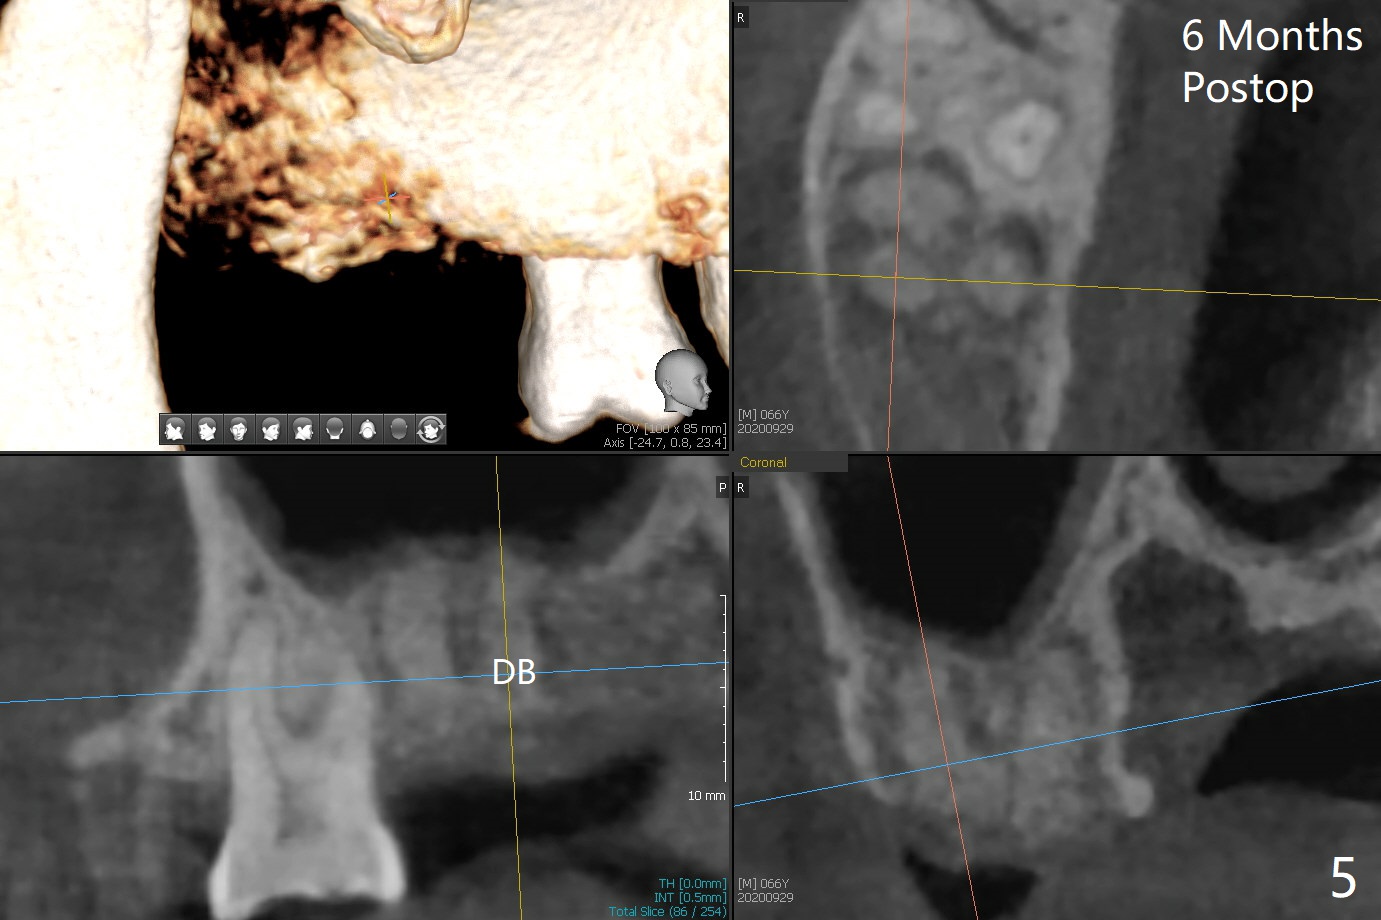

The apices of the mesio-buccal (MB) and disto-buccal (DB) roots are soft when the tooth #2 is extracted. After socket debridement, there is no air leak. Minera-lized cortical and cancellous mix (50/50) hydrated with ~ .25 ml of .3 mg/ml of rhPDGF-BB is placed in MB and DB sockets and pushed upward with a curette. Finally the whole socket is filled up to the crest and a piece of 8x8 mm BioXclude is placed and sutured in placed with 4-0 PGA (Fig.1-3). In fact sinus lift is accomplished moderately MB and DB (Fig.2,3). In fact the density of the bone graft 6 months postop remains the same as immediate postop, similar to the native bone as well (Fig.4,5). With socket preservation, a longer implant will be placed at #2 (Fig.6, as compared 8.5 mm at #15 without bone graft).